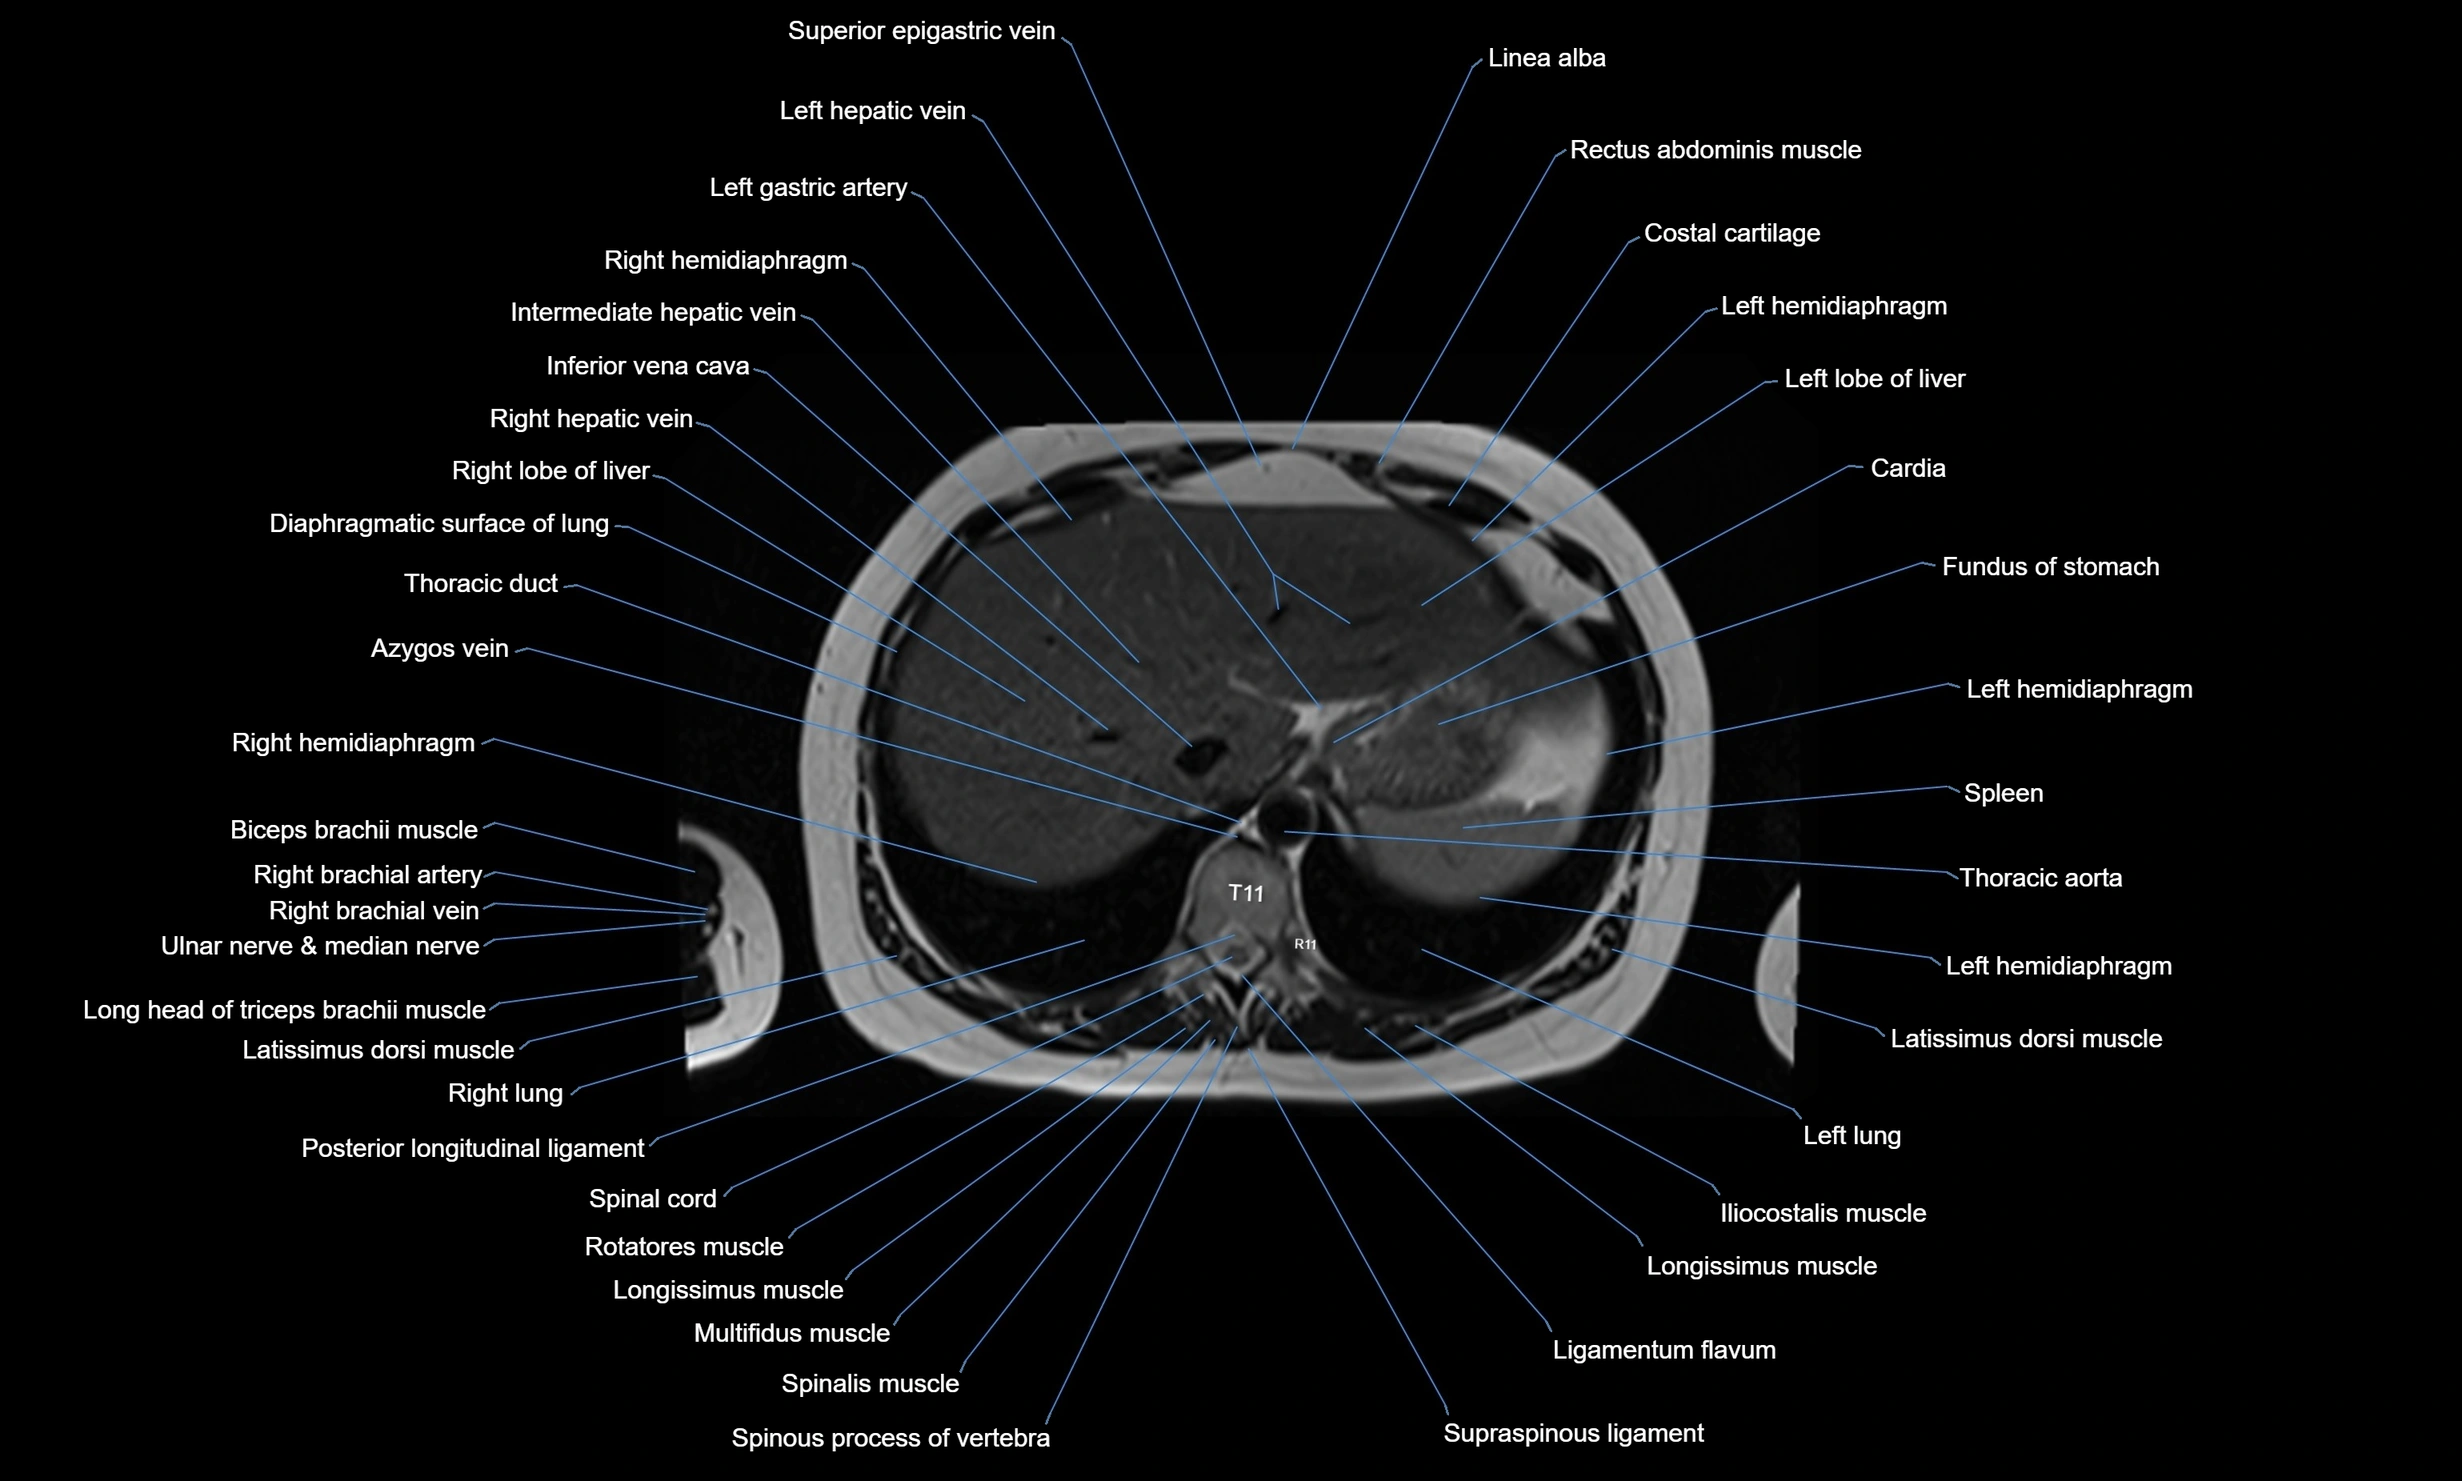

MRI images